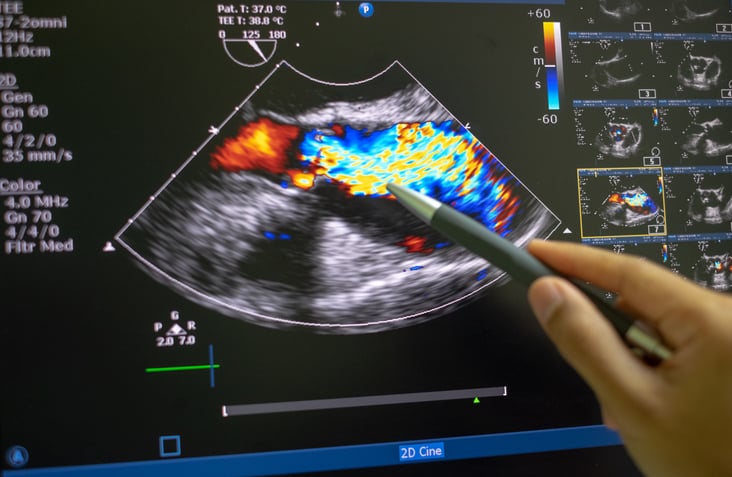

L'ATTR è una malattia rara causata da una mutazione nel gene transtiretina (TTR) che causa un accumulo delle proteine TTR mal configurate come fibrille amiloidi in più organi e sistemi inclusi i nervi, il cuore e il tratto gastrointestinale. Chi ne soffre va incontro nel tempo ad un accumulo di queste proteine anomale che portano, nel tempo, alla progressiva perdita di funzione degli organi maggiormente colpiti. Uno dei distretti più colpiti è il cuore. Diagnosi tardive e sintomi non specifici complicano la gestione della malattia che è spesso sottostimata come causa di insufficienza cardiaca. Poter ridurre l'attività del gene TTR è la chiave per ridurre il danno da accumulo.